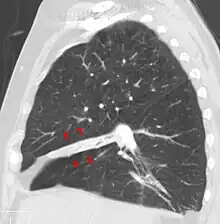

Rounded atelectasis

In rounded atelectasis (folded lung or Blesovsky syndrome[15]), an outer portion of the lung slowly collapses as a result of scarring and shrinkage of the membrane layers covering the lungs (pleura), which would show as visceral pleural thickening and entrapment of lung tissue. This produces a rounded appearance on X-ray that doctors may mistake for a tumor. Rounded atelectasis is usually a complication of asbestos-induced disease of the pleura, but it may also result from other types of chronic scarring and thickening of the pleura.